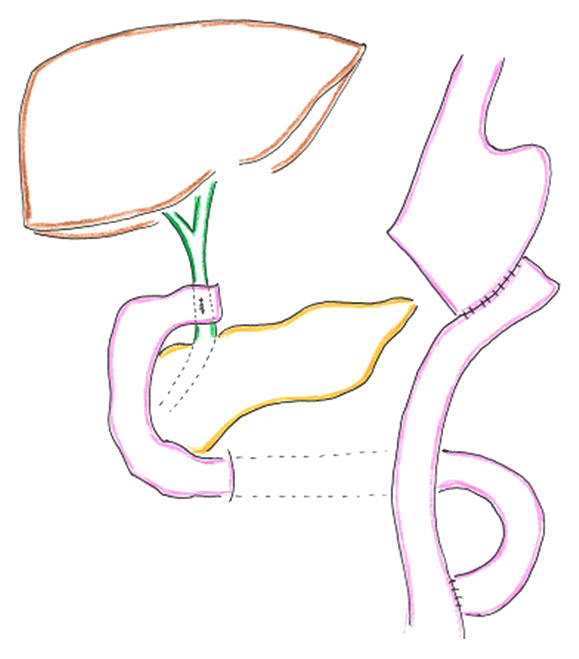

既往歴:6年前,胃癌(幽門側胃切除術,Roux-en-Y再建後),1年前,胆囊結石,総胆管結石,傍乳頭十二指腸憩室症候群(胆囊摘出術,胆管十二指腸吻合術)(Fig. 1)

Schema of distal gastrectomy in this patient undergoing bile duct duodenostomy after Roux-en-Y reconstruction.